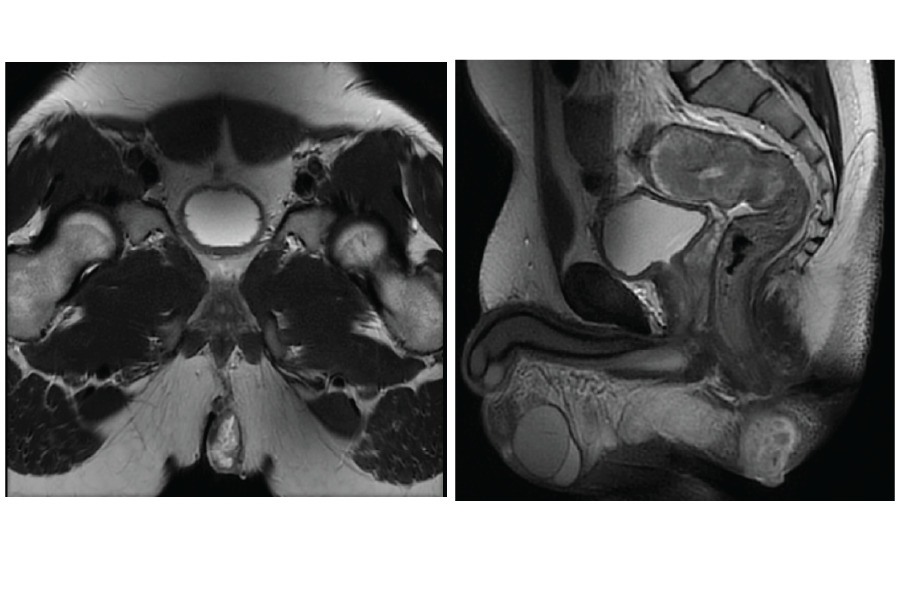

The colonoscopy (Figure 4) revealed proctocolic polyposis involving the anal canal. A polypectomy was performed, and the tissue histology confirmed benign tubulovillous adenoma. Examination under anesthesia and biopsy 3 weeks later yielded similar histological findings. A pelvic MRI (Figure 5) demonstrated a perianal mass with an extrasphincteric fistula approximately 4 cm from the anal verge.